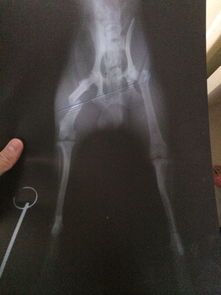

看了你追加描述和圖片,基本確定是骨折!不打算去醫(yī)院的話就按照我上面說的做,狠狠心找到骨折的地方,試著做一下整復,外邊用硬紙殼固定!可以去買一些人藥!狗狗會很快好起來的

我家狗狗一歲之前前腿骨折, 拍片和你這個情況看起來差不多. 沒有做麻醉和內固定手術. 做的是外固定, 不過做好外固定以后就要注意補鈣, 一個月左右, 就好了. 平時要看好它. 不能讓它亂動, 特別是睡覺之前要確定它能正常躺下, 躺下和站起來的過程是比較痛的. 小狗的恢復能力比人強很多, 他們的代謝速度是我們的好幾倍. 所以也不需要太擔心了. 但是如果一定要做手術的話, 鋼針一定要取出來的. 至于麻藥的風險, 不能說沒有. 我家的做絕育手術也用了全身麻醉, 有各別狗狗會有過敏性休克. 但是幾率很低.至于這個南瓜子,我沒有喂過. 不過如果是我要喂狗狗吃的話, 應該會磨碎或者弄小顆拌狗糧, 它就會吃. 我家的是吃貨, 不挑食的. 假如挑食的話, 可以稍微烤一下嘛, 香一點自然會吃啦! 其實狗狗真的好的很快的. 最主要的是看好它不要讓它亂動重復受傷, 如果接好了以后固定住了又錯位, 就很麻煩了. 還有接不好或者又亂動錯位了還給長好了, 就很可能變成長短腿或者Z型腿. 如果對你有幫助記得采納哦。